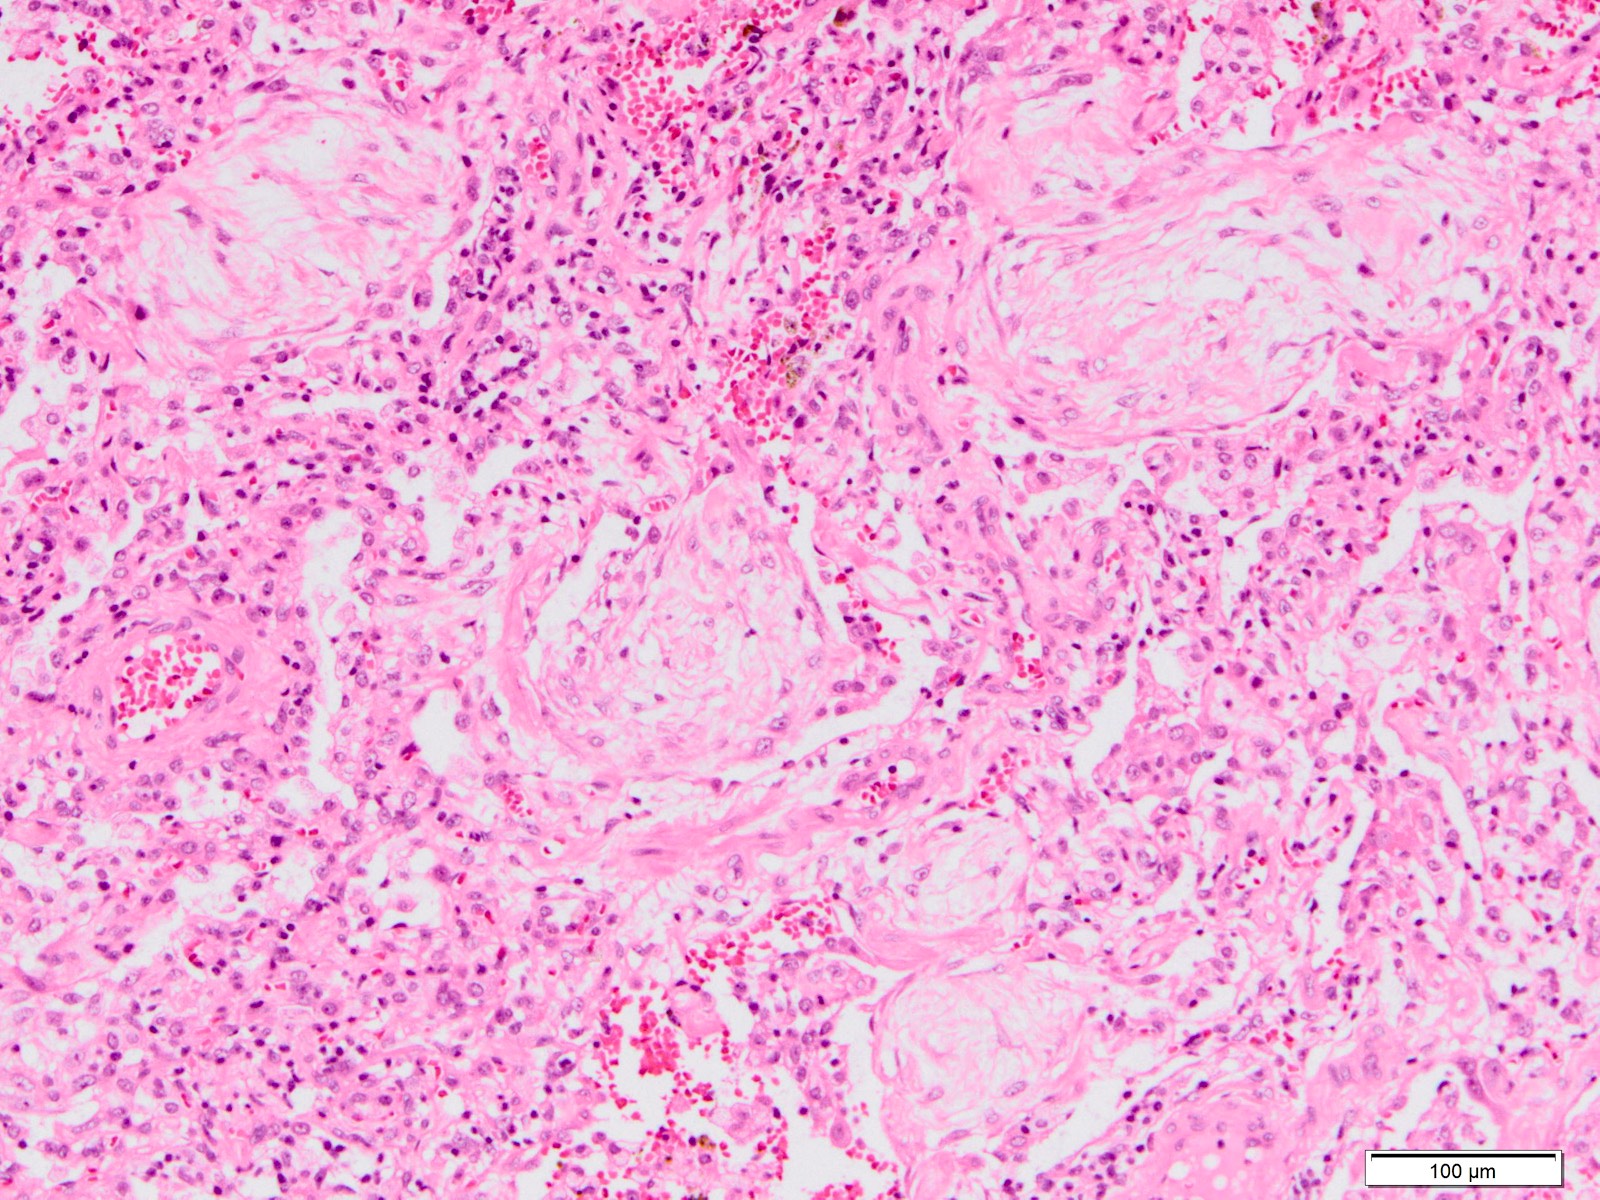

Microscopic (histologic) description

- Histopathology of DAD progresses from exudative (acute) phase through proliferative / organizing (subacute) phase to chronic fibrotic phase roughly corresponding to the period of ARDS (Am J Pathol 1976;85:209, Arch Pathol Lab Med 2010;134:719, Clin Chest Med 2000;21:435, N Engl J Med 2000;342:1334)

- Proliferative / organizing (subacute) phase

- Alveolar change

- Remnants of hyaline membrane with or without organization

- Interstitial and intra-alveolar proliferation of myofibroblasts

- Lymphocytic infiltration

- Epithelial change

- Proliferation / hyperplasia of type II pneumocytes

- Vascular change

- Endothelial injury and thromboemboli in arterioles

- Alveolar change

- DAD with prominent organizing pneumonia is also called organizing DAD

Microscopic (histologic) images

Contributed by Akira Yoshikawa, M.D. and Yale Rosen, M.D.